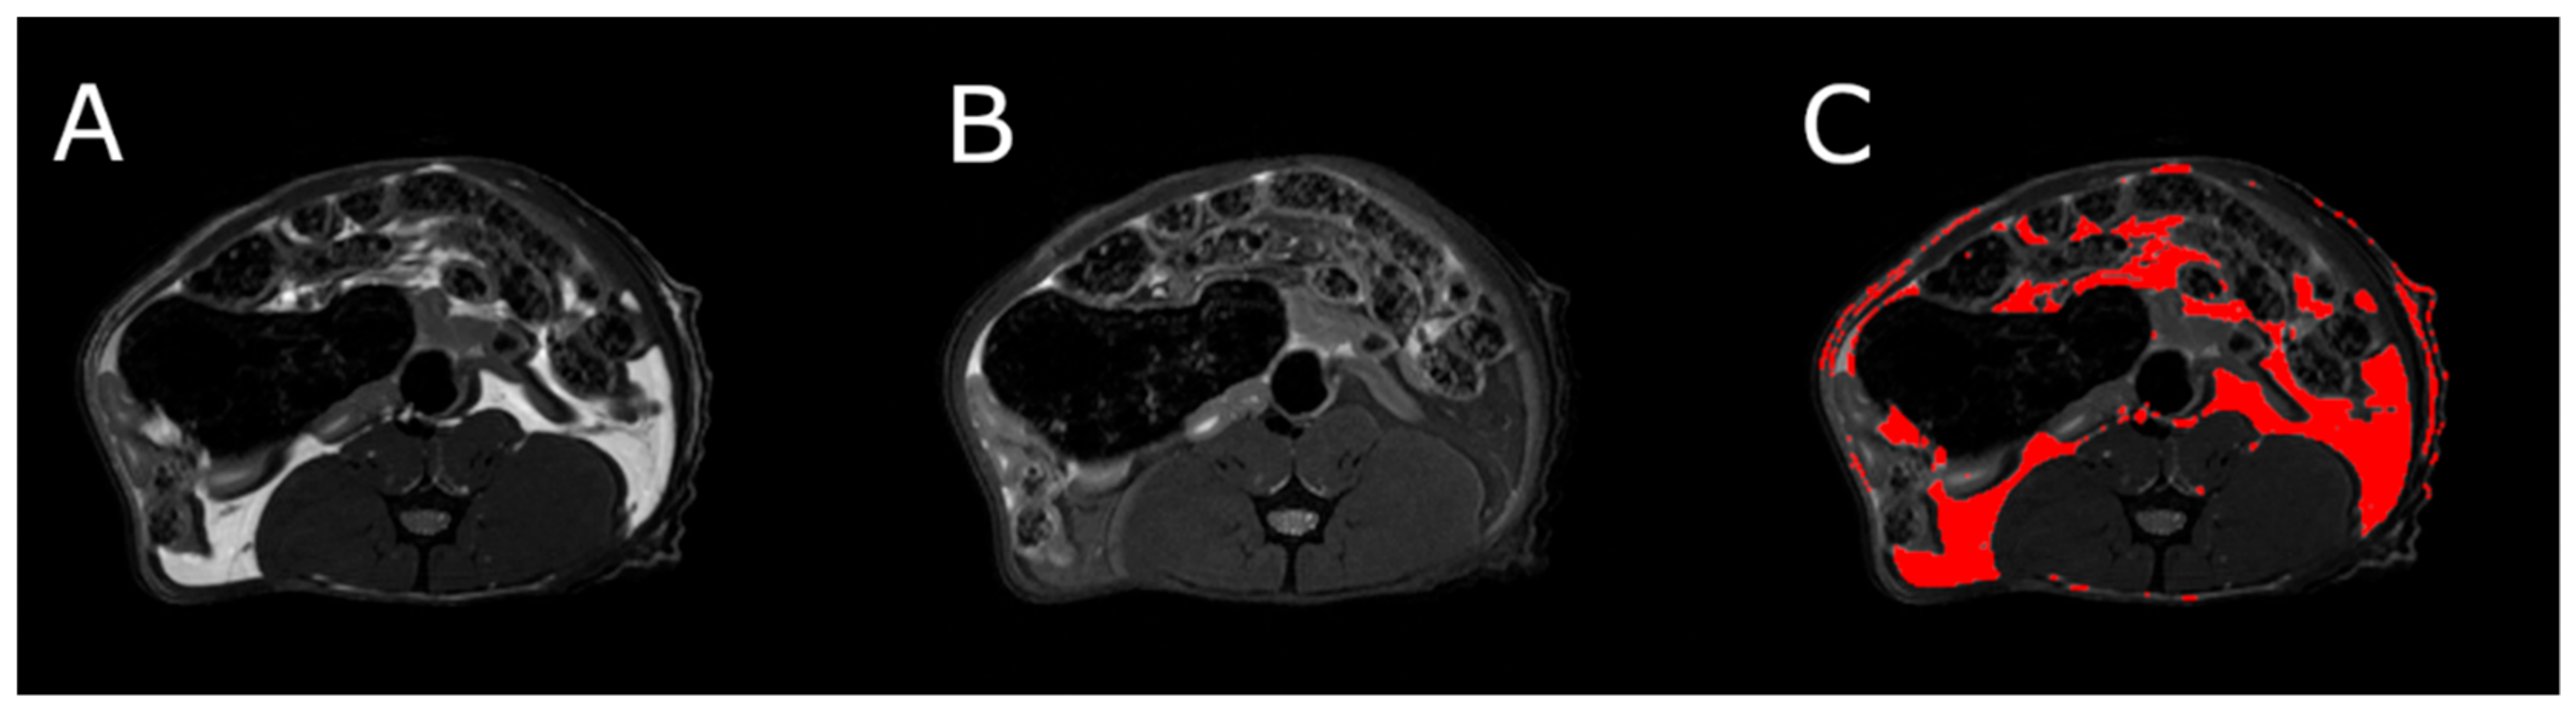

MRI measurements showed a significant reduction in the adipose tissue volume of ABA rats compared with controls (Figure 5). The mean visceral body fat reduction in the ABA rats reached 58.9% on day 6 of the experiment (Figure 6).

Figure 5.

MRI scan of female healthy rat, the cross section of the abdomen at L4 level. (A) RARE image without fat suppression; (B) fsupRARE image with fat suppression; (C) segmentation result—adipose tissue marked in red.

MRI was used to determine the volume of visceral and subcutaneous adipose tissue at the level of the L4 vertebra in healthy and ABA rats. MRI experiments were performed on a 9.4T Bruker Biospec scanner, using a Bruker T9361 transmit/receive birdcage coil with a diameter of 72 mm. Animals were euthanized with pentobarbital prior to imaging (Morbital, Biowet, Pulawy; 1–2 mL/kg b.wt.) after ketamine/xylazine premedication to obtain high-quality images devoid of any artifacts. Imaging was performed using the fast spin-echo rapid acquisition with a relaxation enhancement sequence (RARE). Pulse sequence parameters were echo time = 6.3 ms, repetition time = 2000 ms, RARE factor = 8, acquisition matrix = 256 × 256, field of view = 60 × 60 mm, and number of slices = 23. The entire abdomen from L1 to L6 was covered with 1 mm thick axial slices. Imaging was done twice, first without fat suppression (RARE) and repeated with the fat suppression module (fsupRARE) turned on. In the images obtained with the spin-echo sequence, fat appears as a bright area. This area becomes correspondingly darker when fat suppression is used. This relationship was used to find image pixels containing fat. Adipose tissue segmentation was performed using a custom-developed MATLAB script (The Mathworks, Inc.). The slice passing through the L4 vertebra in the reference anatomical image was selected for further analysis. First, the pixel values of both images were normalized to 1. The difference between the normalized RARE and fsupRARE images was then calculated—the fat containing pixels were those for which the difference image pixel value was greater than 0.2. Finally, adipose tissue volume was calculated as the product of the number of pixels containing fat and the volume of a single pixel.